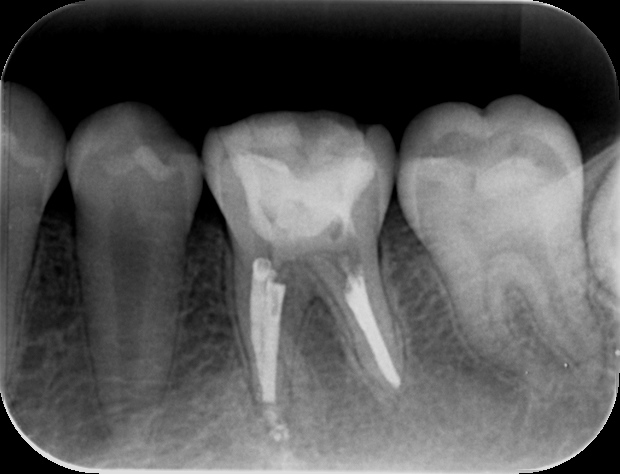

【再治療後の状態】 再治療後のデンタルX線写真(後日掲載予定)をご覧いただくとわかるように、病変は消失しており、根管内にも薬剤がしっかりと行き届いている様子が確認できます。 根尖孔外に漏れていたMTAには変化はありません。